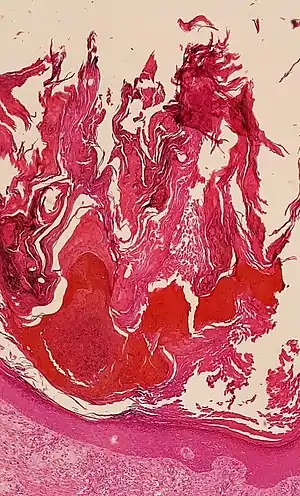

![]() Histologic image of human epidermis in thick skin. | |